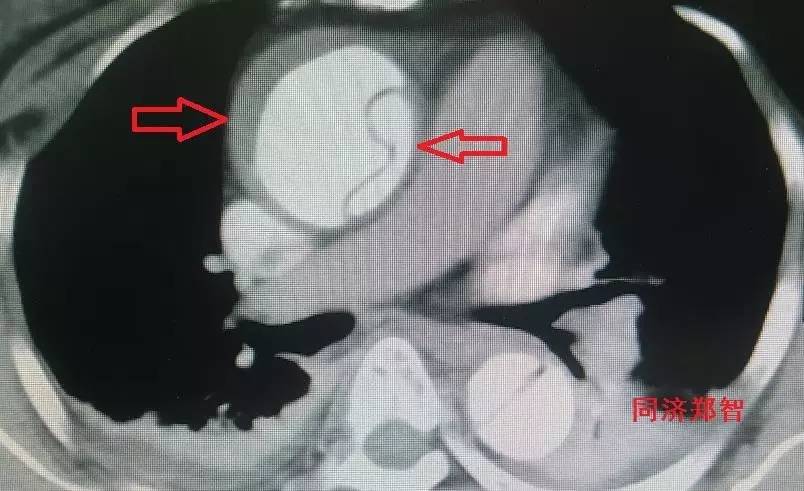

CTA显示升主动脉穿透性溃疡合并壁间血肿(图13)。

图13

CTA显示降主动脉穿透性溃疡合并Stanford A型主动脉壁间血肿(图14)。

图14